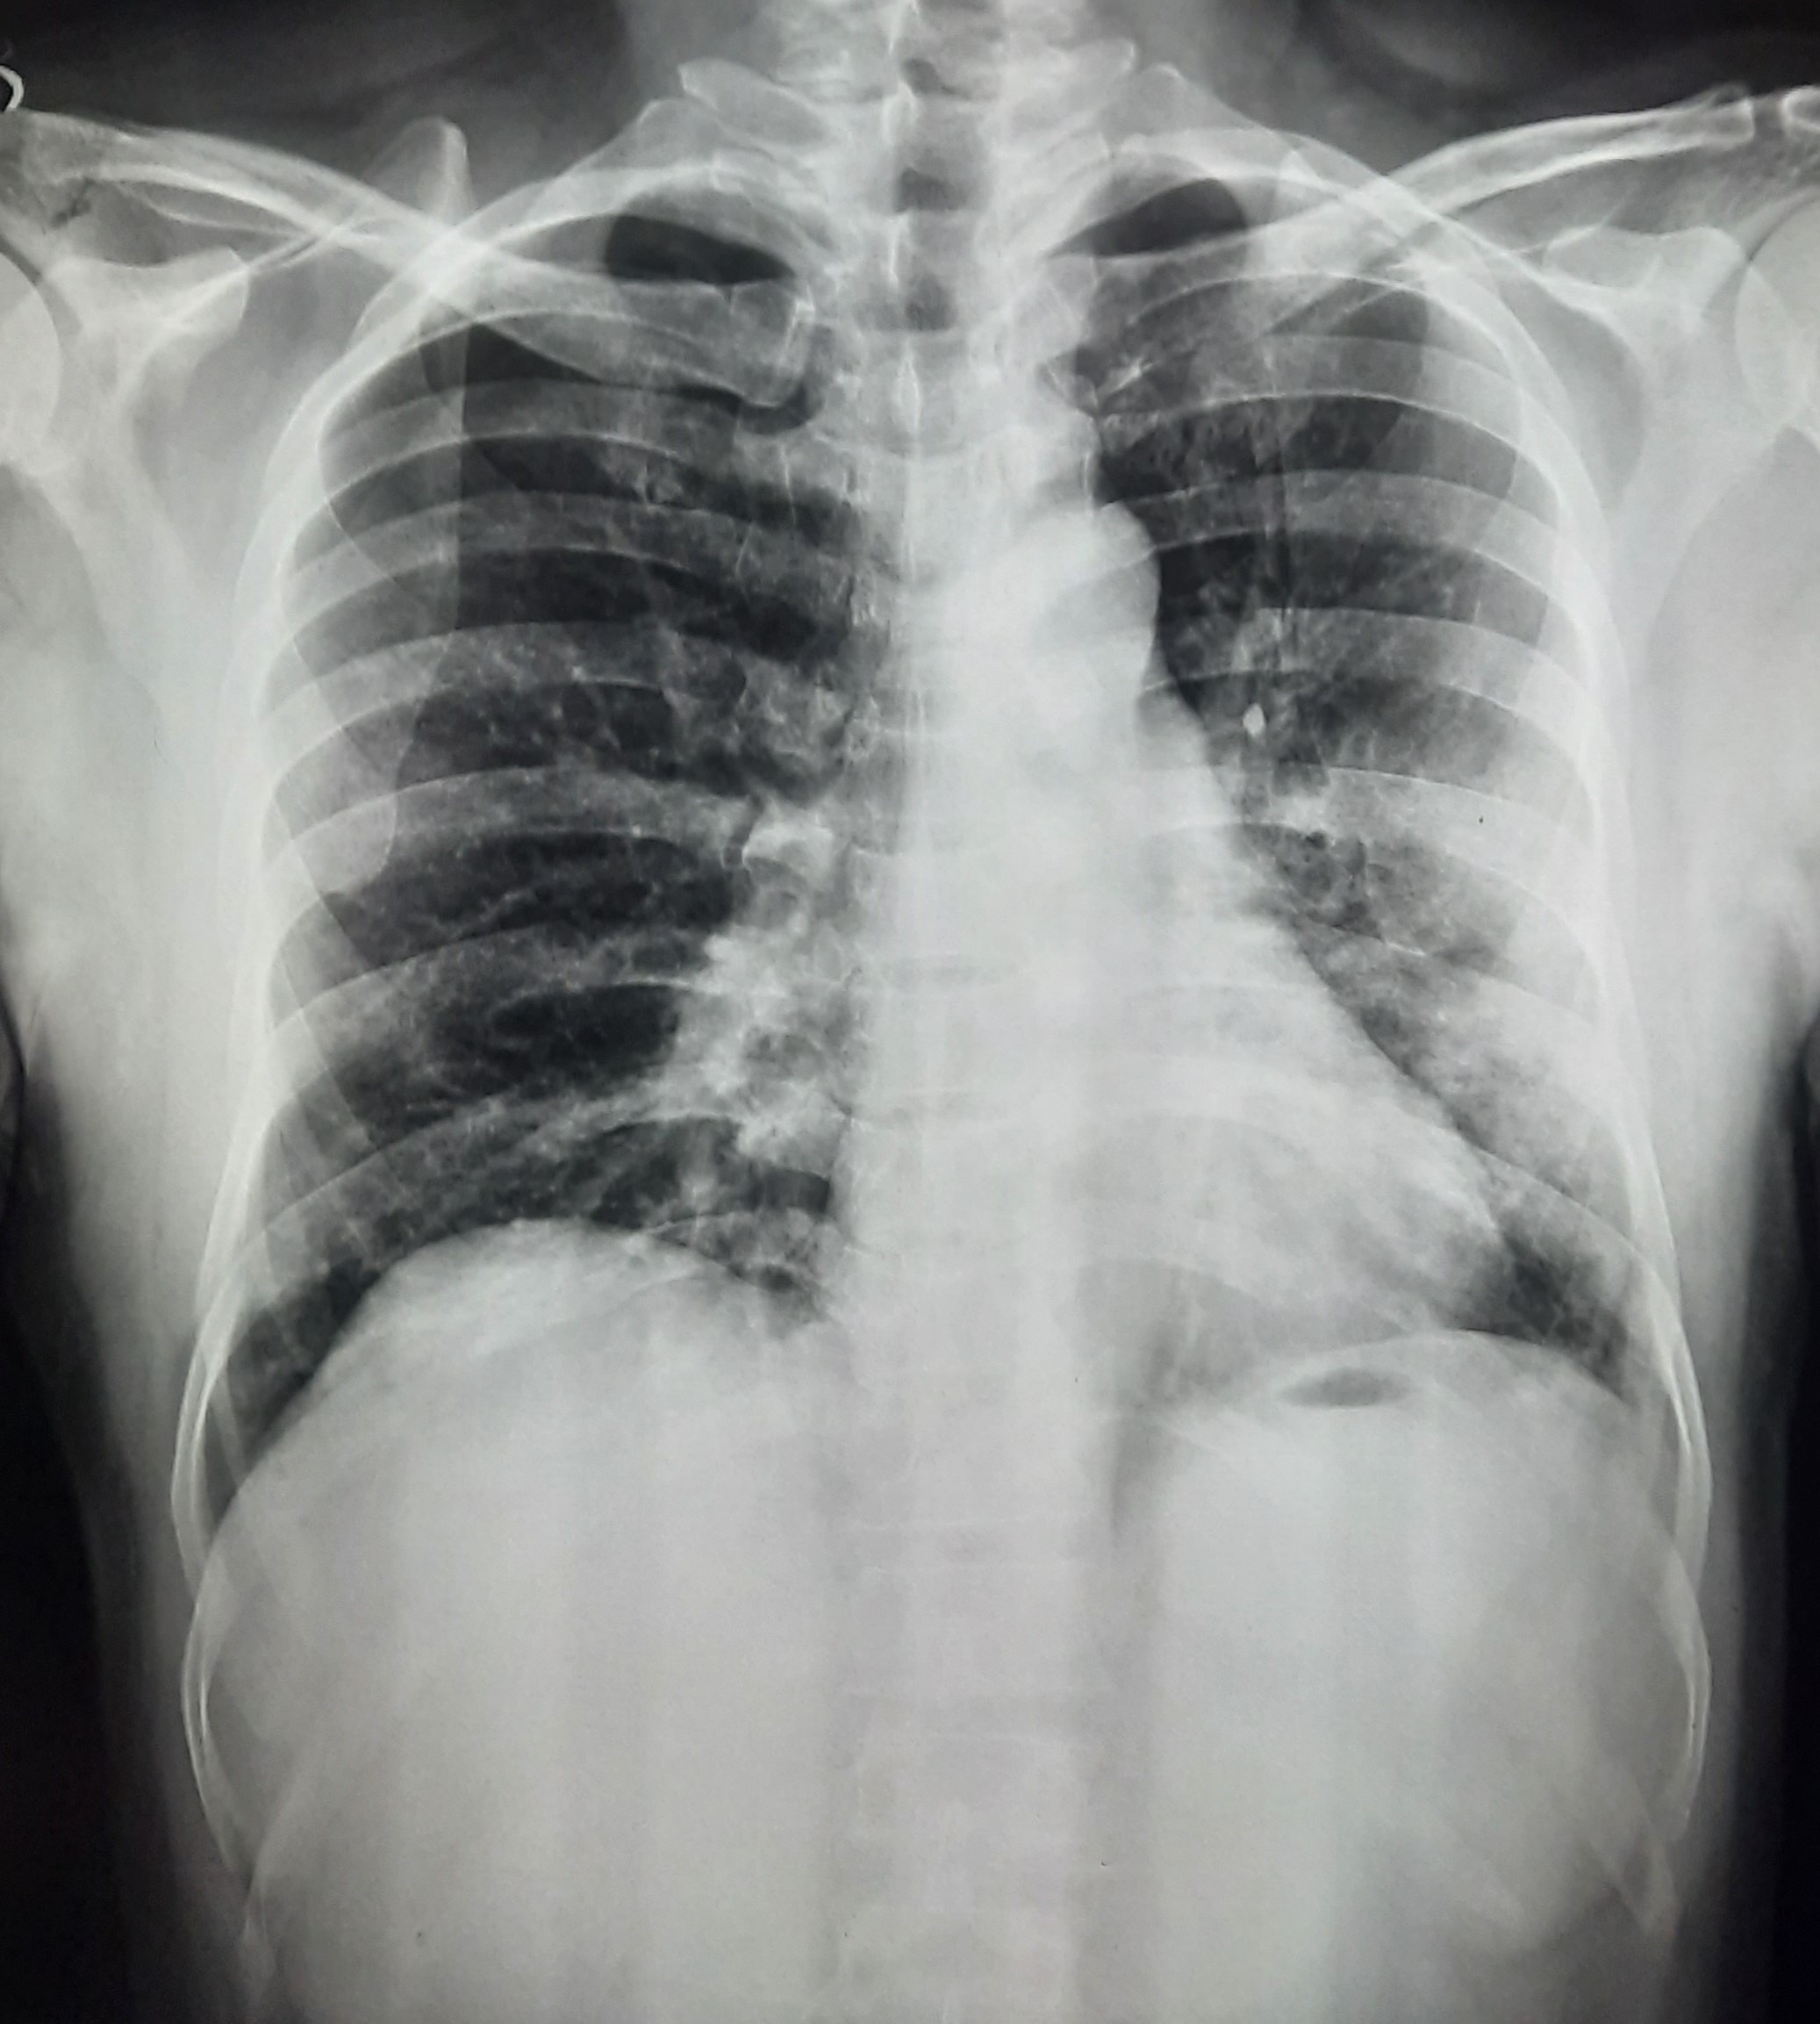

| 51 | IGGMC, Nagpur, Nagpur | P2 | 29-4421 | Santosh Neware | Consent taken on Paper | 40 Yrs. |

Provisional Diag : Pulmonary Tuberculosis

Final Diag : Pulmonary tuberculosis (Microbiologically Confirmed PTB) |

TB Case (Confirmed) | Right Upper & mid zone fibro cavitary lesion present, upward pull of right hemidiaphragm, tracheal pull right sided | Abnormality visible on x-ray |